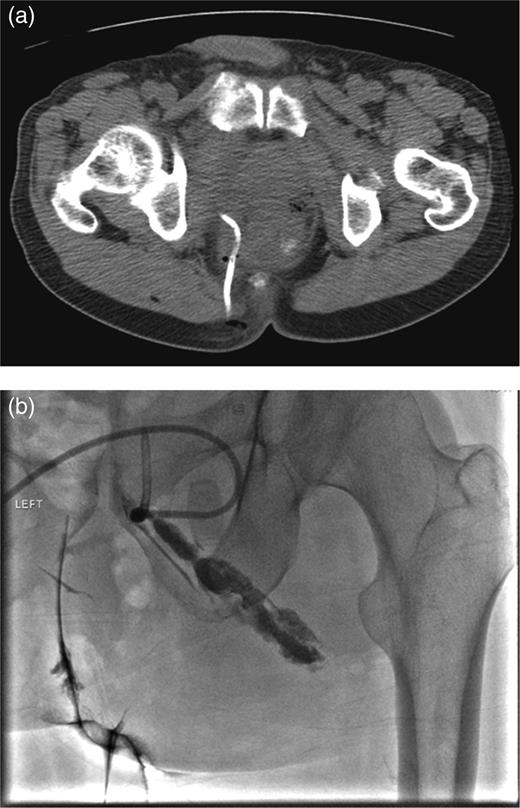

In the 6-week follow-up, repeat CT demonstrated eccentric thickening of the rectosigmoid with interval development of an adjacent complex pelvic fluid collection with supralevator extension measuring 3.5 × 2.5 cm (Fig. 2a and b). Percutaneous needle biopsy revealed pus, and a drainage catheter was left in place (Fig. 3a and b). The patient did not improve, was reimaged and was found to have collection extending into the ischiorectal fossa and supralevator space (Fig. 4). Owing to refractory pain and persistent leukocytosis, the patient was taken to the operating room for examination under anesthesia. No fistulous tract or internal drainage was noted within the rectal vault; however, consistent with the imaging, external induration was observed along the right ischiorectal fossa, where, upon incision, a large purulent cavity was evacuated. On evening rounds, the patient was noted to have a marked leukocytosis and frank stool coming from the ischial wound, and he was taken emergently to the operating room for diagnostic laparotomy where a perforated diverticulum adherent to the pelvic sidewall was identified (Fig. 5). Therefore, a Hartmann procedure, drainage of supralevator abscess, irrigation and debridement of the right ischiorectal wound, was performed.

(a) CT-guided percutaneous drainage of perirectal abscess (b) fluoroscopic drain study showing contrast extending into the supralevator space.